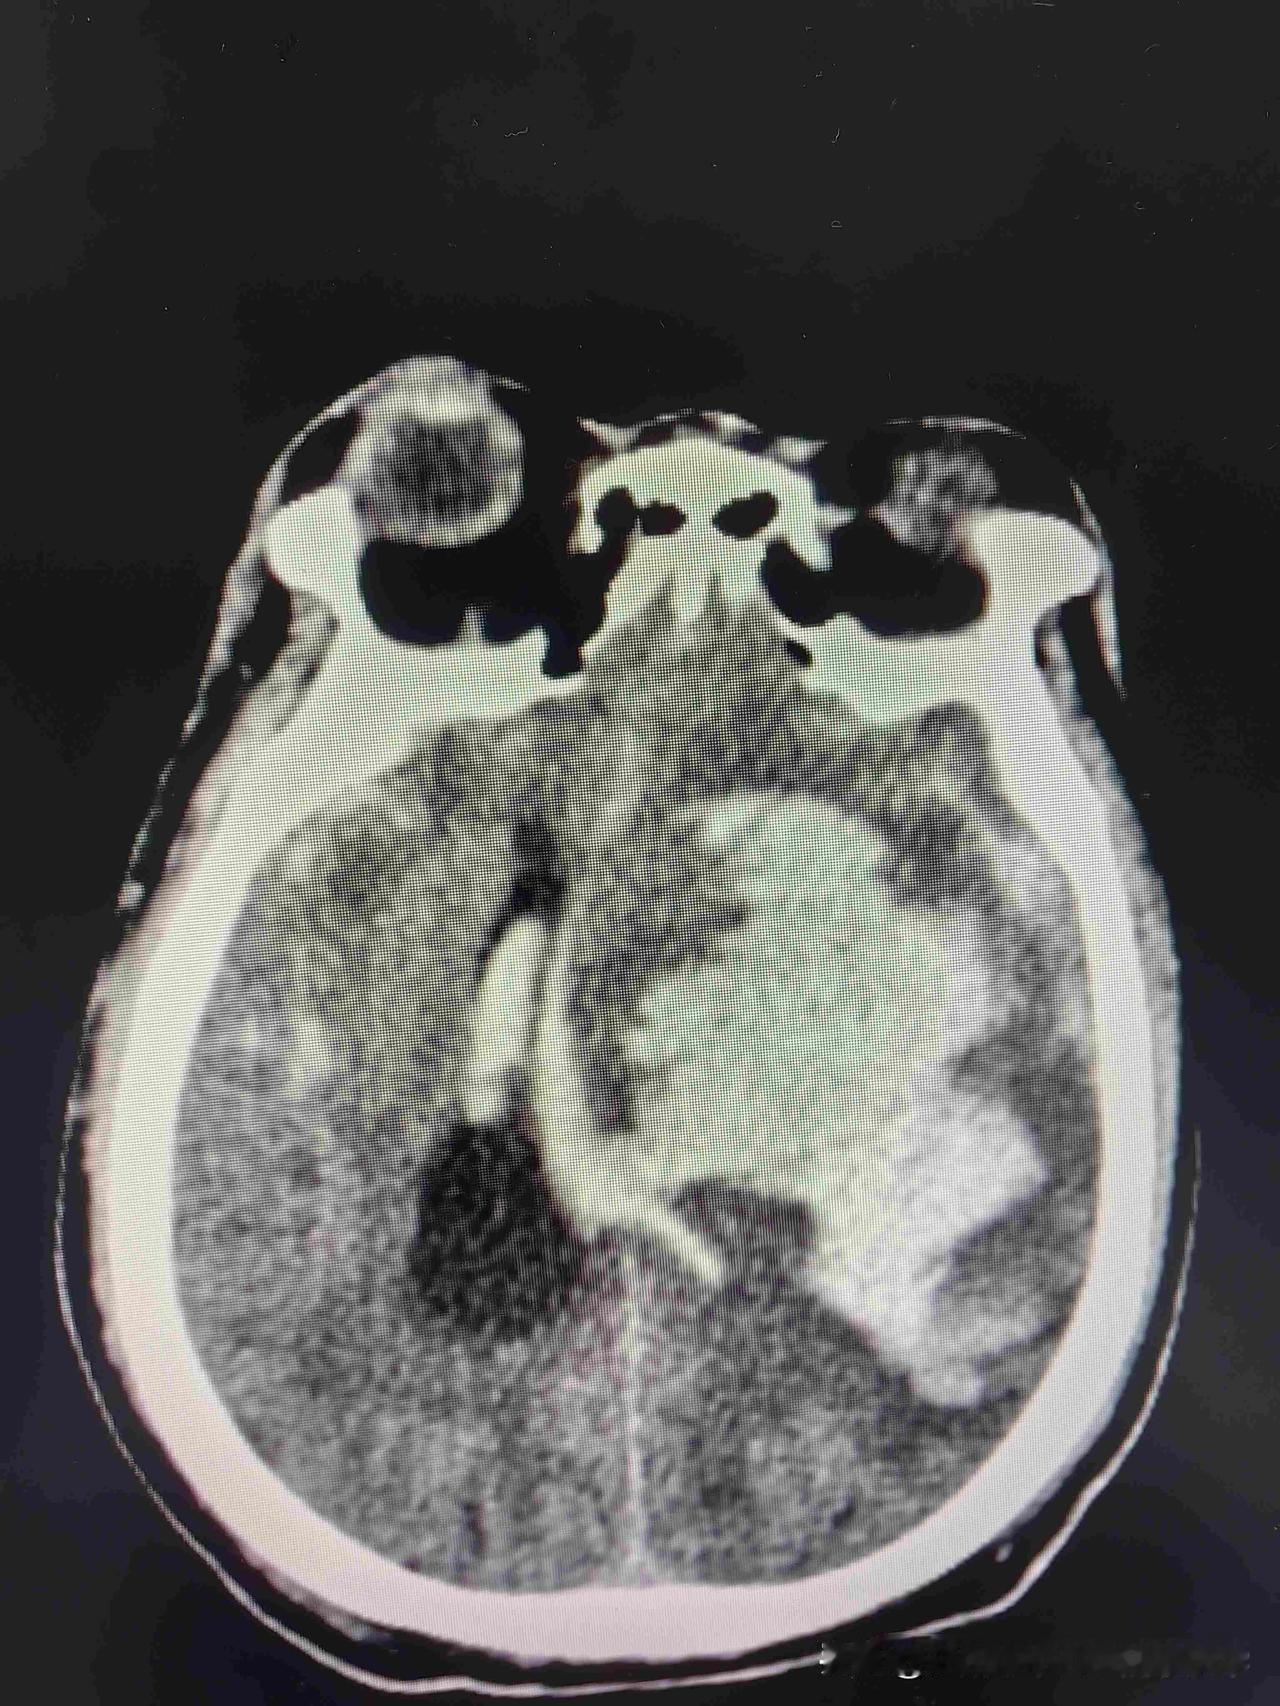

还有治疗的价值吗? 前天晚上,张大哥照例跟朋友打牌,打到很晚,走的时候还笑着喊,再来一局,谁也没想到,这竟是他最后的样子,第二天早上,他爱人推开门,一股味道冲得她差点站不住,人躺在床边,缩着,裤子湿了,嘴边全是吐出来的脏东西,叫了好久,一点反应都没有。 医生说他脑里出血太多,一边瞳孔已经散了,随时可能停呼吸,急救室走廊里,他儿子攥着检查单,手一直在抖,我爸要是能活下来,以后绝对不让他碰酒瓶了,可谁都明白,这话早该在半年前说,村里人都知道,张大哥每天准点喝半斤白酒,打牌时有人劝他少喝点,他总摆手,我这身子骨结实着呢。 急救灯闪到凌晨,护士猛地冲进家属室,说瞳孔开始散了,他老婆一下扑到床头柜上拍得砰砰响,早听我的去锻炼,早听孩子的话去体检,能落到这步田地吗,抢救室外的走廊里,几个亲戚低着头默默抽烟,烟雾里飘着一句,这回真没机会了。 急救室外的长椅上,他儿子盯着墙上的心电图线,一上一下,跟张大哥的日子一样,本可以平平稳稳过,却总往边上凑,手机响了,妻子发来张照片,急救床上,父亲半边脸肿得发紫,手还死死攥着昨晚打牌赢的两张红桃。